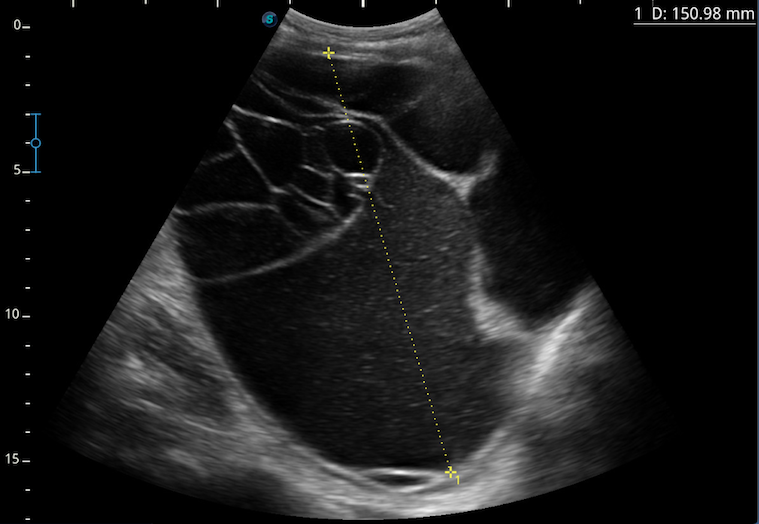

En la exploración se aprecia abdomen distendido, depresible, no doloroso a la palpación. Sin signos de irritación peritoneal. Se palpa masa a nivel de pelvis hasta hipogastrio. Resto de exploración sin alteraciones. Ante estos hallazgos en la exploración se realiza ecografía abdominal en consulta, visualizando una formación con múltiples tabiques que parece depender de ovario derecho y que ocupa toda la pelvis, desplazándose hasta el ombligo. Ante la sospecha de origen ovárico se deriva a la paciente a Ginecología para completar el estudio.

En la ecografía abdominal se evidencia una masa quística, de contornos bien delimitados, multitabicada de unos 15 cm que depende de ovario derecho y que ocupa toda la pelvis, desplazándose hasta hipogastrio.